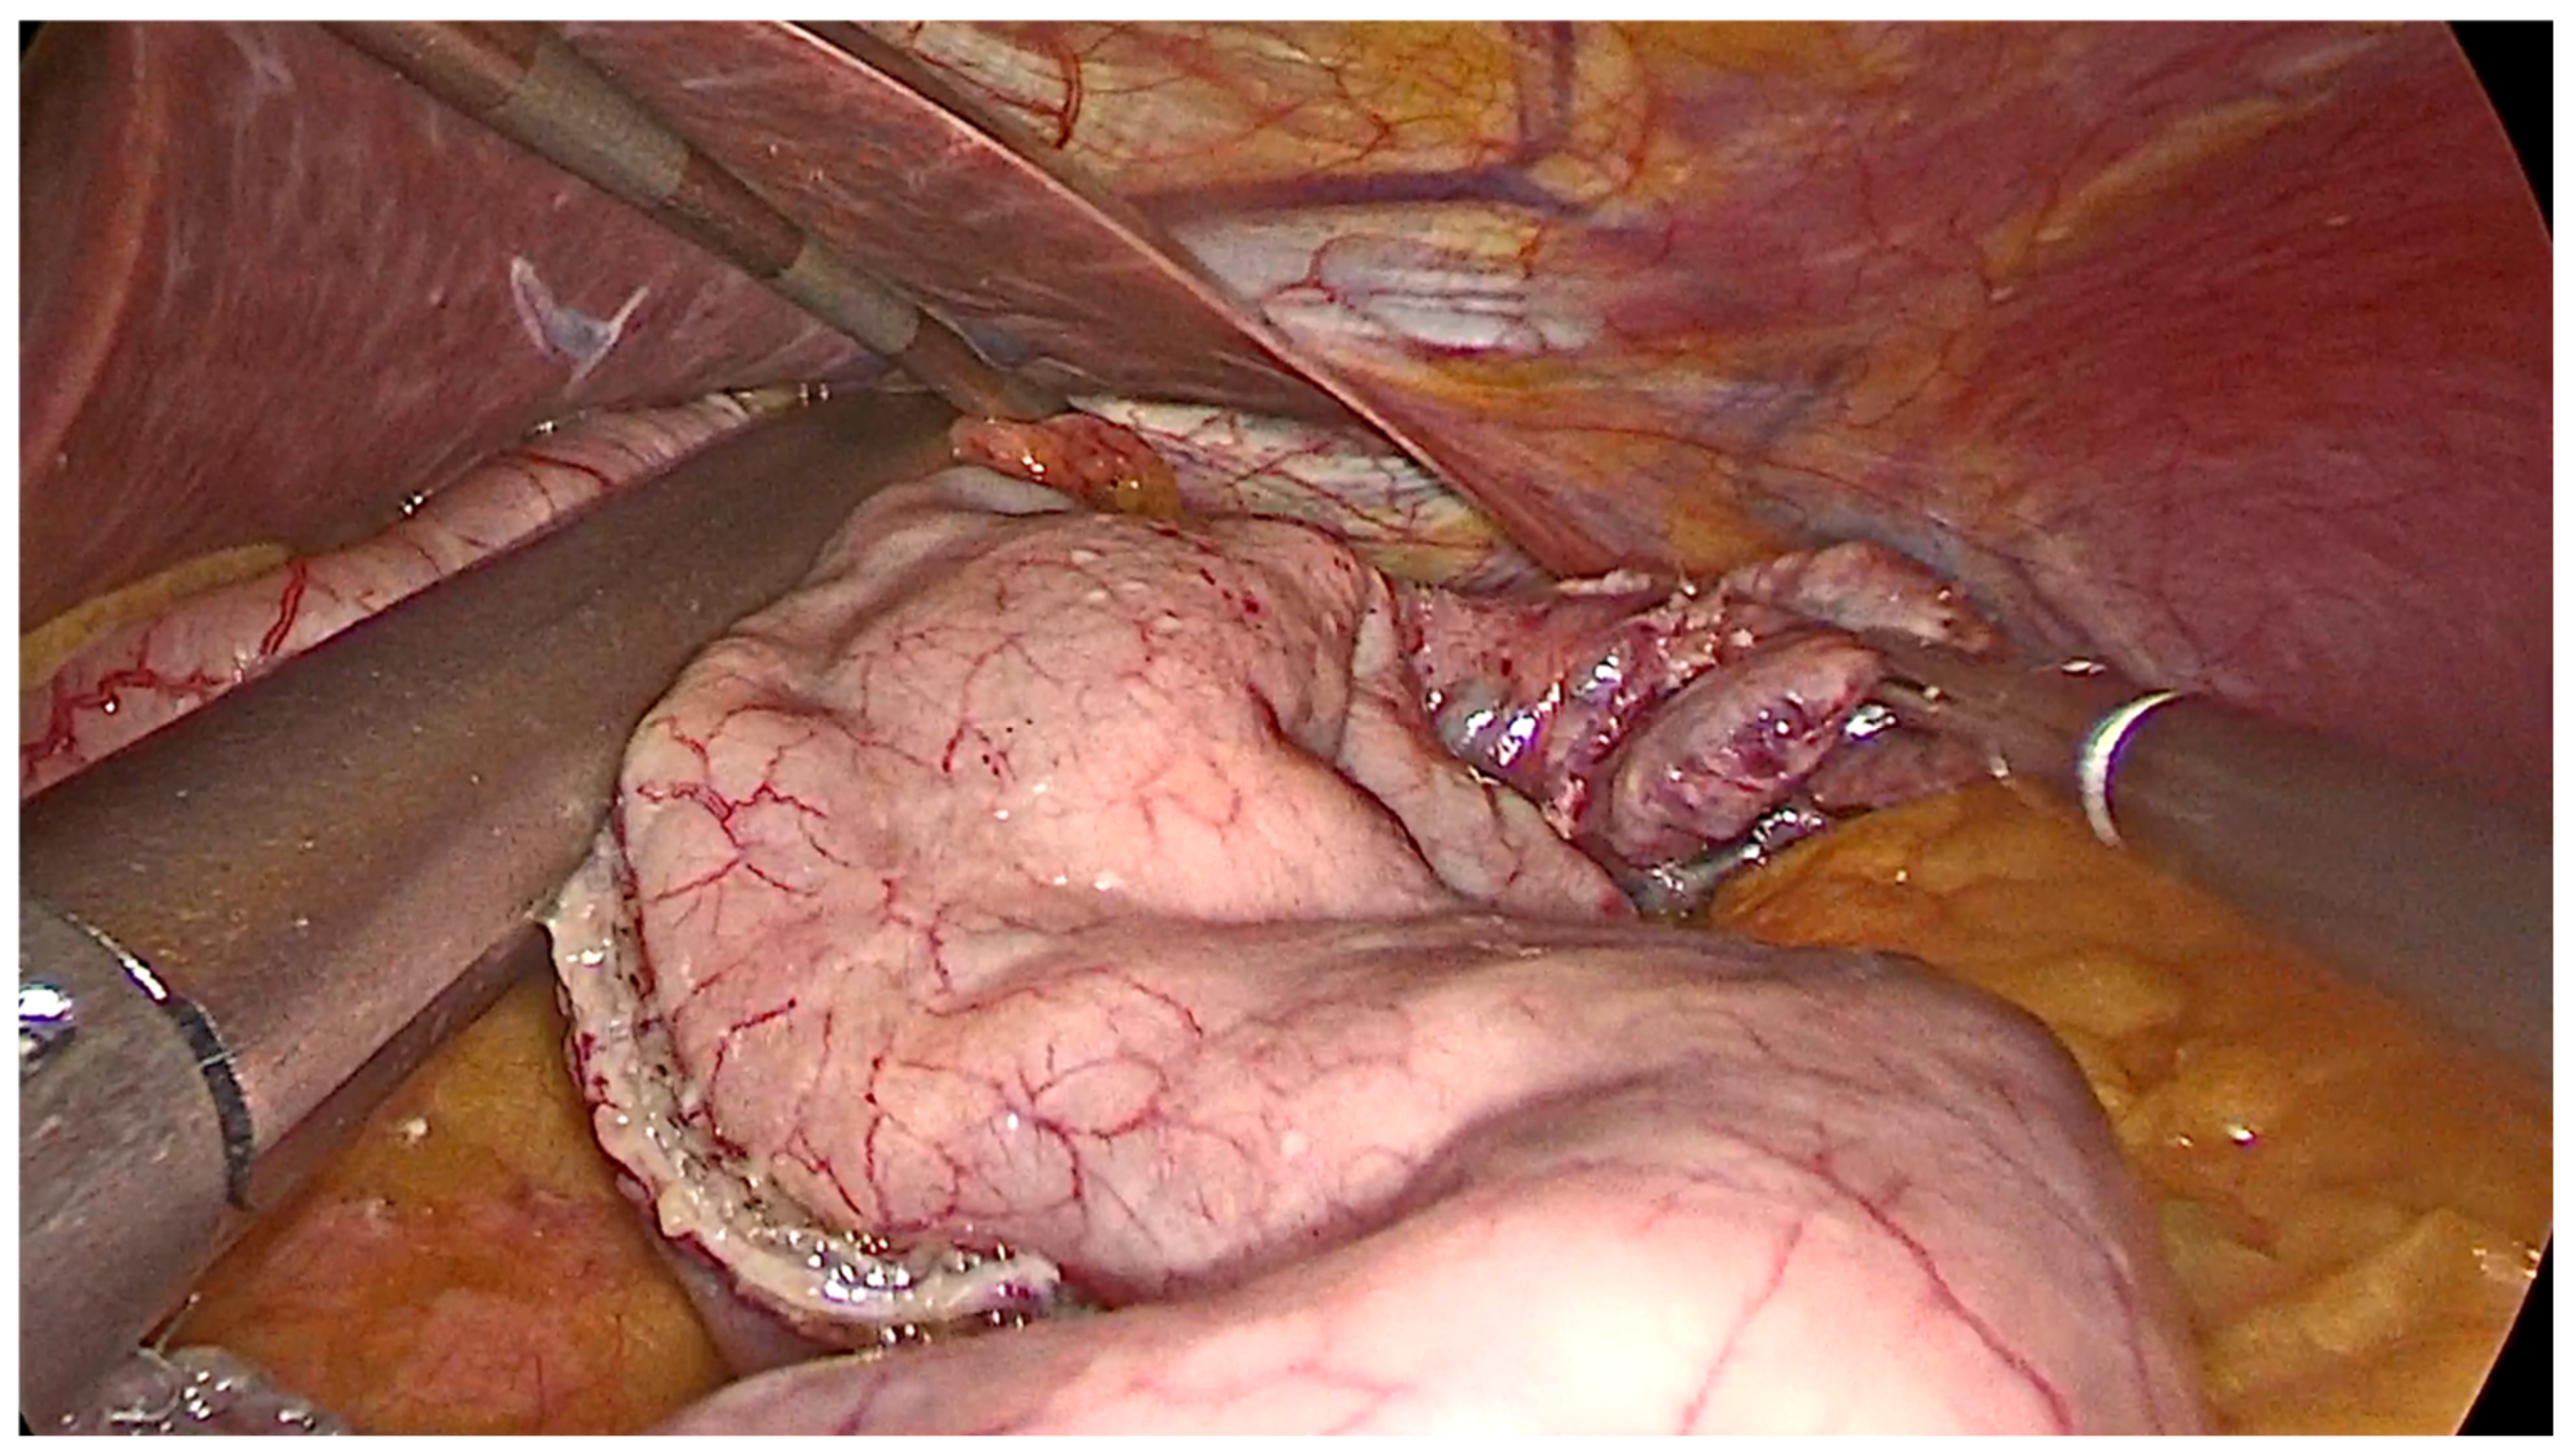

1.2. Technical Considerations

- Opening a window in the gastro-colic ligament using an energy device from the antrum and proceeding up to the angle of His, along the greater curvature, until the left diaphragmatic pillar was fully exposed.

- The gastric fundus must be entirely mobilized with coagulation and section of the short gastric vessels and the opening of the gastro-splenic ligament.

- After the transoral position of a bougie (of diameter ranging 36–40 Fr), sleeve gastrectomy is performed with the use of a stapler, beginning from the distance of 4–6 cm from the pylorus up to the angle of His.